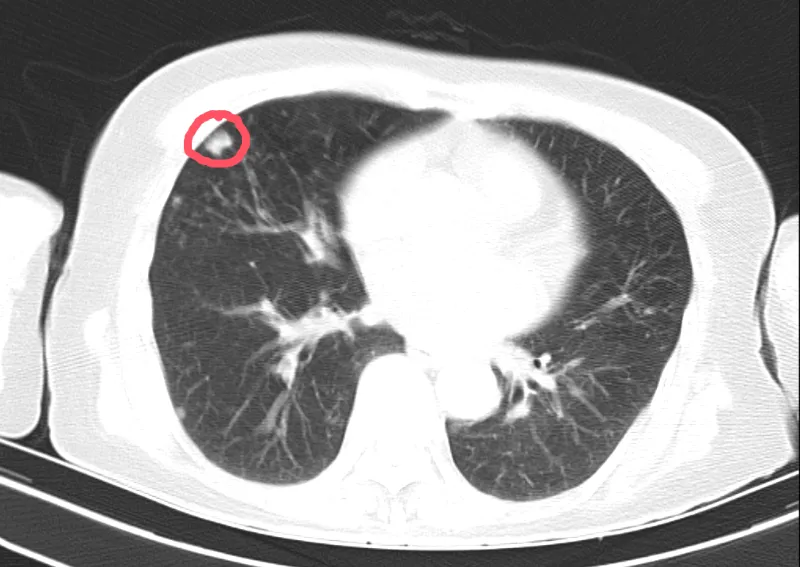

72岁的余婆婆因发现右肺中叶有实性结节,就诊于黄陂区中医医院肺病科(呼吸内科),复查胸部增强CT提示余婆婆肺结节靠近胸部外侧,结合结节大小已达12mm,科室团队在全面评估和深入讨论后,决定为患者实施经皮肺穿刺活检术,进一步明确结节性质,为后续治疗提供科学依据。

肺结节是指肺部影像上各种大小、边缘清楚或模糊、直径小于等于3cm的局灶性圆形致密影,是一种常见的肺部病变,它通常不会引起任何症状,但是有时候会变成恶性肿瘤。医生提醒:一旦发现肺结节,要及时就诊,定期复查,必要时需行进一步检查以明确诊断,避免耽误病情。